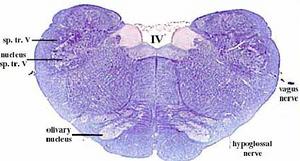

secciones transversales a diferentes niveles del tronco del encéfalo mostrando la localización de los núcleos neuronales eferentes de los nervios craneales

EFERENTES:

somatoeferentes (SE) : inervan músculos esqueléticos

visceroeferentes(VE): parasimpáticos

Núcleo espinal del V o núcleo del tracto trigémino, localizado en la médula oblongada, y está asociado con la sensación del dolor y temperatura de la mitad de la cara.

Aferentes viscerales generales (GVA): localizados laterales a la columna GVE y compuesto por un único núcleo denominado núcleo solitario o núcleo del tracto solitario, el cual está asociado con IX y X, recibiendo la sensación visceral de la faringe, laringe y porciones del esófago.